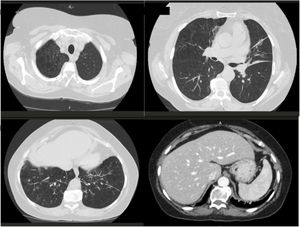

Respiratory complications became less frequent once AAT augmentation therapy started. Still, the patient had on average two exacerbations per year of an infectious nature with a total of seven hospitalizations in four years. After achieving a diagnosis of AATD the patient underwent a chest tomography scan to evaluate the extension of lung disease. This revealed bilateral bronchiectasis, mostly in basal regions, and centrilobular and paraseptal emphysema, mainly in superior lobes (Fig. 1).